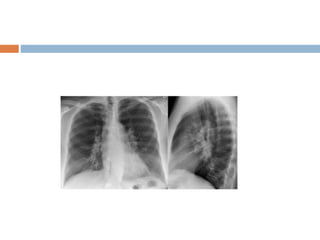

D/W PA and AP view

PA VIEW AP VIEW

Scapula Seen in periphery of thorax Seen over lung fields

Clavicles project over lung fields Above the apex of lung field

Ribs Posterior ribs distinct Anterior ribs distinct

Spine Clearly seen not clearly seen